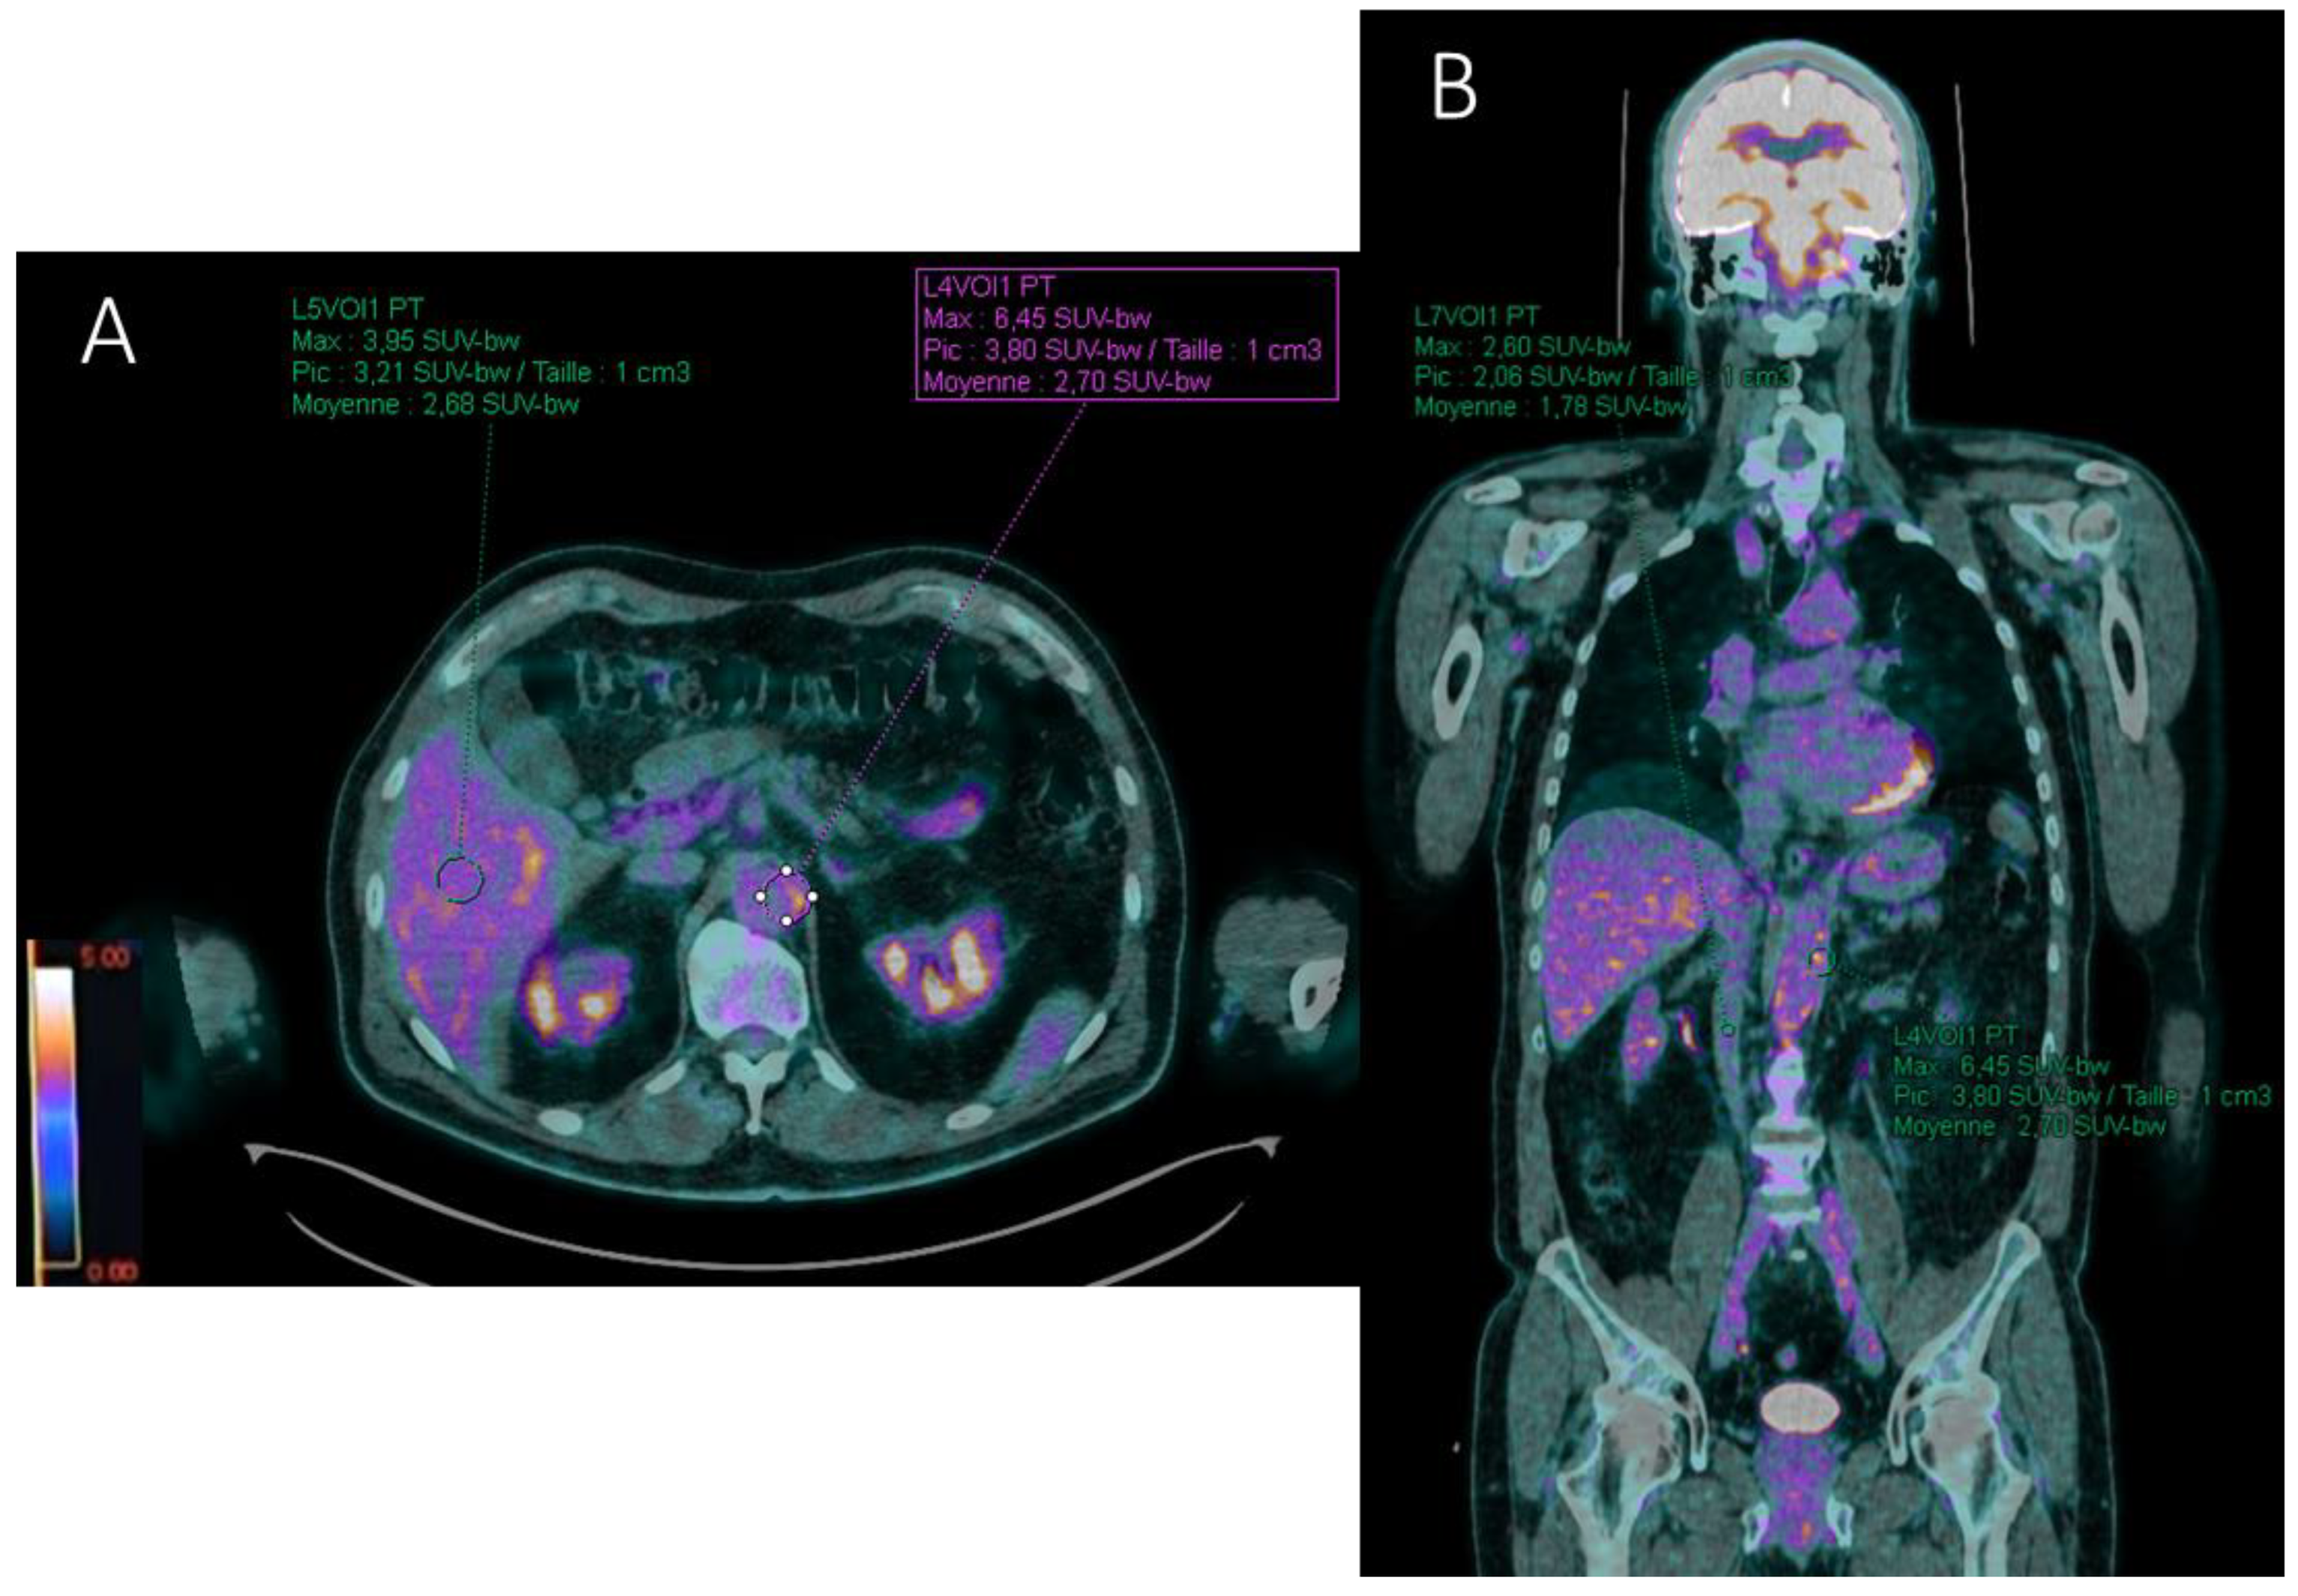

- Target-to-liver ratio (TBRliver) by placing a ROI in the healthy right lobe of the liver;

- Target-to-blood pool ratio (TBRblood) defined for supra-diaphragmatic vessels by a ROI drawn centrally in the blood pool of the superior vena cava and for infra-diaphragmatic vessels in the blood pool of the inferior vena cava.